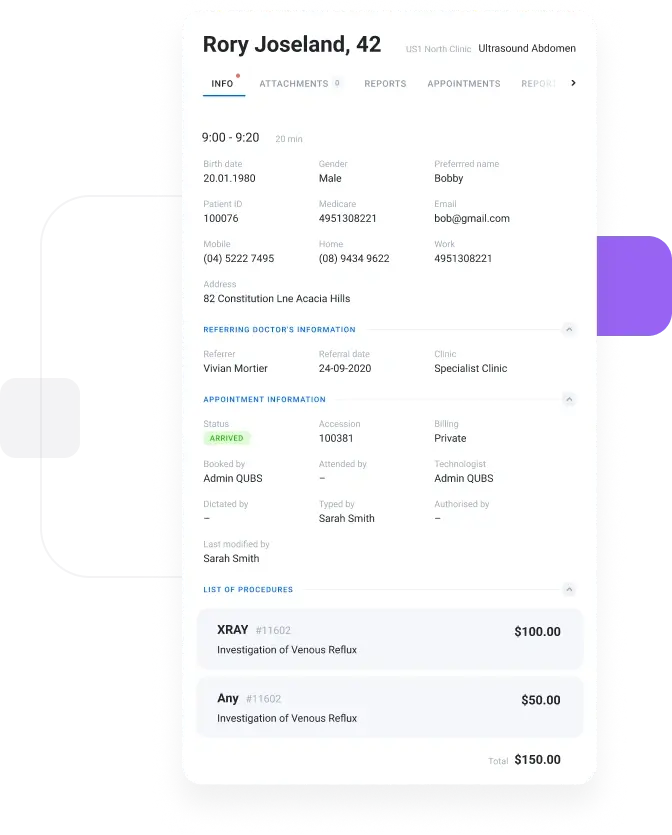

Open studies instantly

with a zero-footprint

viewer

Give radiologists and referrers browser-based access to current studies and priors without installing heavy desktop software at every location.